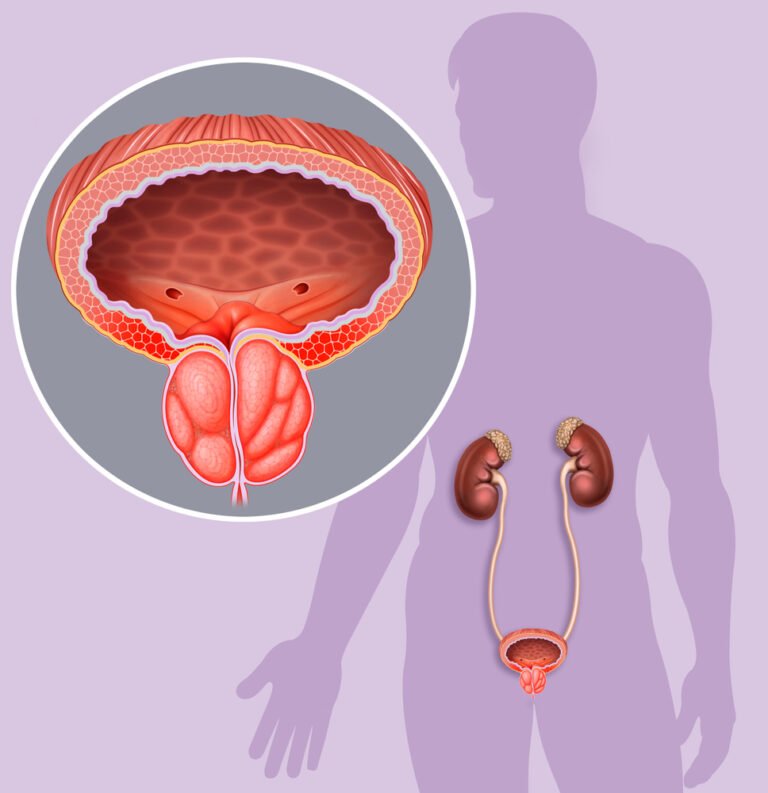

Mencari cara mengatasi nyeri prostat adalah langkah penting bagi pria dalam menjaga kesehatan sistem reproduksinya. Masalah pada area ini sering kali menyebabkan ketidaknyamanan yang dapat mengganggu aktivitas sehari-hari mereka.

Penderita sebaiknya menyadari bahwa deteksi awal gejala nyeri berpengaruh signifikan terhadap keberhasilan pengobatan di masa mendatang. Mengambil langkah-langkah pengobatan secara alami bisa menjadi alternatif yang menarik karena cenderung memiliki efek samping yang lebih sedikit.

Pemilihan jenis makanan yang tepat sangat memengaruhi tingkat keparahan gejala yang muncul pada area prostat. Buah dan sayur yang mengandung antioksidan tinggi mampu menekan risiko peradangan lebih lanjut secara efektif.

Penderita sebaiknya mulai rutin mengonsumsi tomat atau brokoli yang kaya akan kandungan zat likopen serta glukosinolat. Nutrisi tersebut bekerja aktif dalam melindungi sel-sel prostat dari kerusakan akibat paparan radikal bebas berbahaya.

Langkah konsisten dalam menerapkan pola makan seimbang merupakan cara mengatasi nyeri prostat yang sangat direkomendasikan ahli. Hindari makanan yang mengandung lemak jenuh tinggi karena dapat memperparah kondisi pembengkakan pada area sensitif.

Pemanfaatan tanaman obat seperti alang-alang, sambiloto, dan juga pegagan memberikan dukungan nutrisi yang sangat baik bagi penderita. Ramuan alami ini bekerja efektif dalam membantu mengatasi gangguan prostat dan juga membantu meredakan gejala awal kanker.

Kandungan aktif di dalamnya berperan penting untuk mengurangi peradangan serta pembengkakan pada kelenjar prostat pria dewasa. Pilihan herbal tersebut merupakan cara mengatasi nyeri prostat yang aman untuk mendukung kesehatan fungsi saluran kemih.